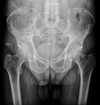

How well did you know this?

1

Not at all